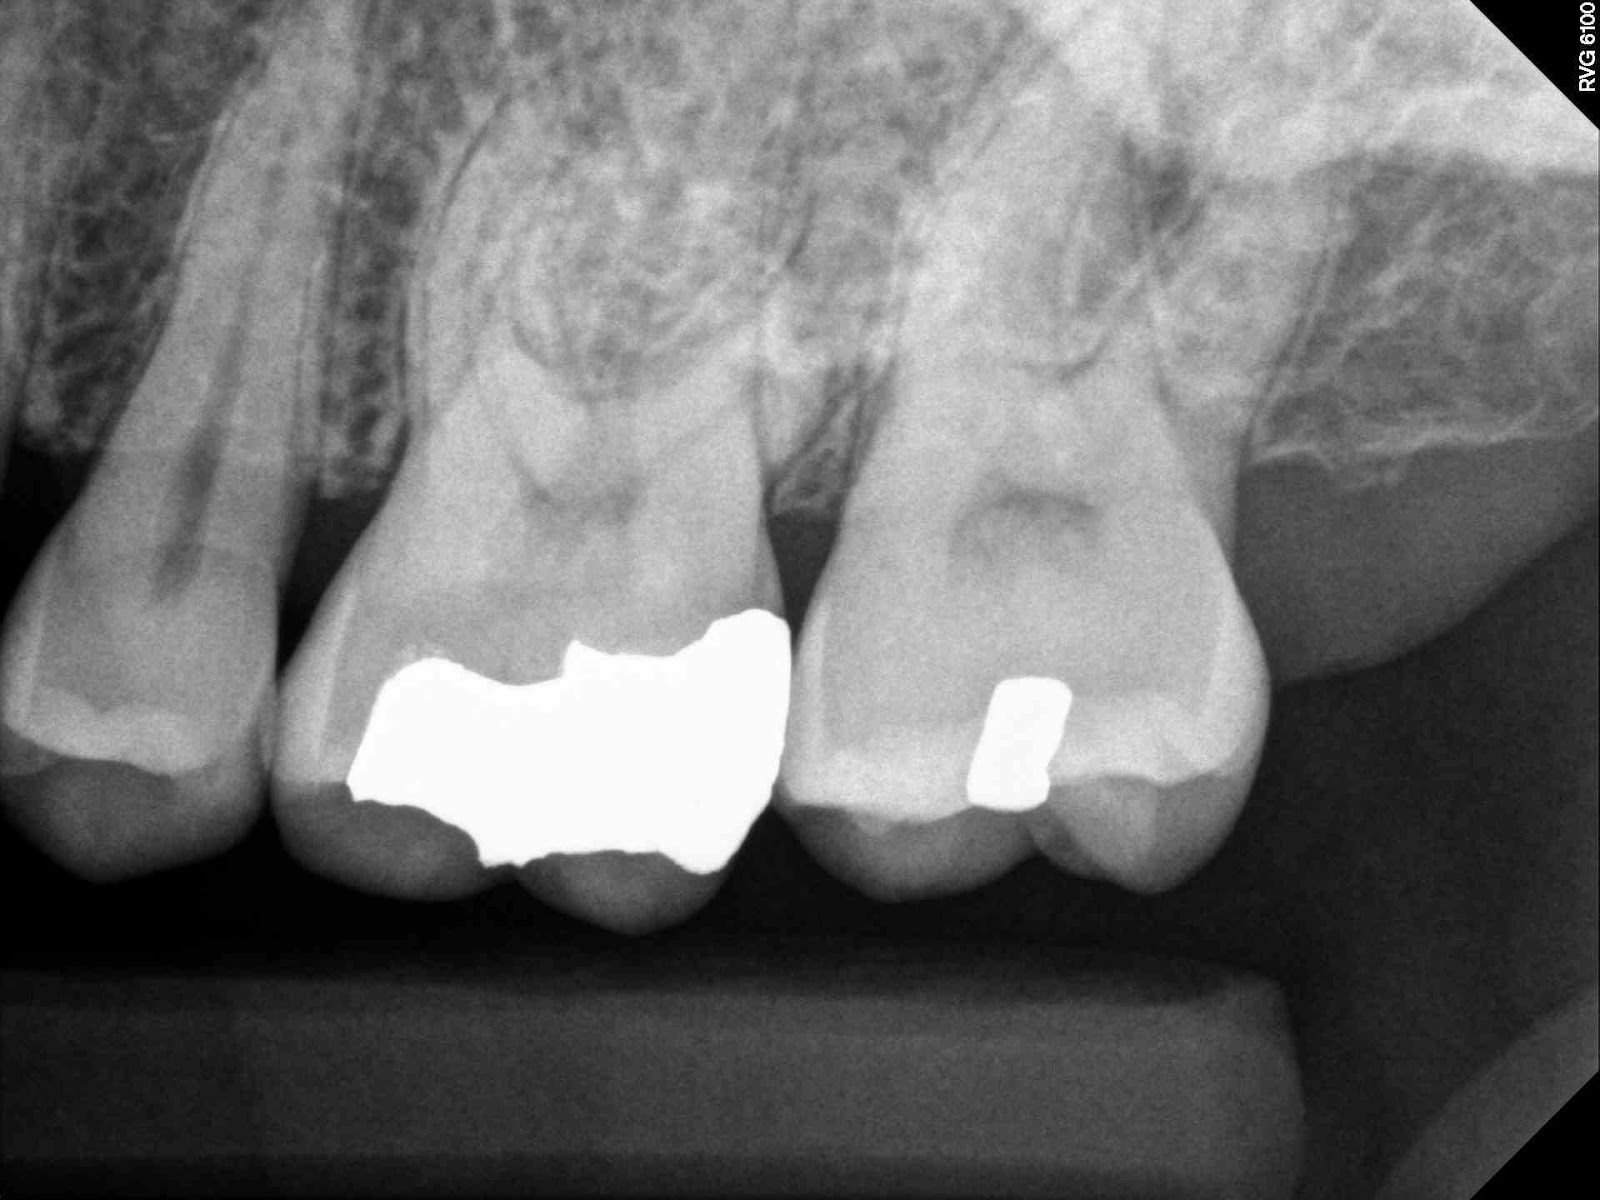

![]() |

| Here looks like MB1 is OK or maybe long depending on how you look at it |